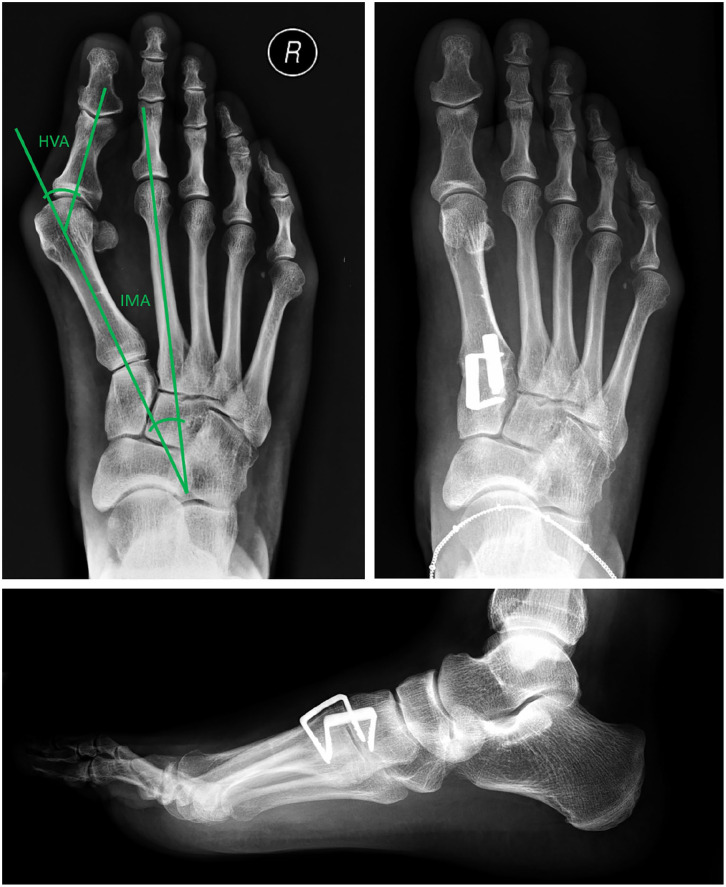

Methods: A total of 60 cases undergoing Lapidus arthrodesis between June 2018 and June 2022 were analyzed with a median follow-up of 37 months (range: 15-64 months). All cases were treated using two nitinol staples (BME EliteTM; DePuy Synthes) for TMT1 fusion. Among these, 38 cases involved additional foot procedures, while 22 cases had isolated TMT1 fusion. Data were collected from medical records, radiographs, and a telephone survey. The hallux valgus angle (HVA) and intermetatarsal angle (IMA) were measured preoperatively and postoperatively on weightbearing dorsoplantar radiographs. Functional outcomes were assessed using the Foot and Ankle Ability Measure-Activities of Daily Living (FAAM-ADL) subscale, and patient satisfaction was evaluated using a 4-point Likert scale.

Results: The TMT1 fusion rate was 96.7% (58/60). The reoperation rate-including hardware removal, revision surgery for recurrence, and nonunion-was 16.7%. The staple breakage rate was 3.3%. The IMA improved from 15.8 to 8.9 degrees (P < .001), and the HVA improved from 37.5 to 17.3 degrees (P < .001). The average FAAM-ADL score was 81.7 out of 84, with 90% of patients reporting being very satisfied or satisfied.